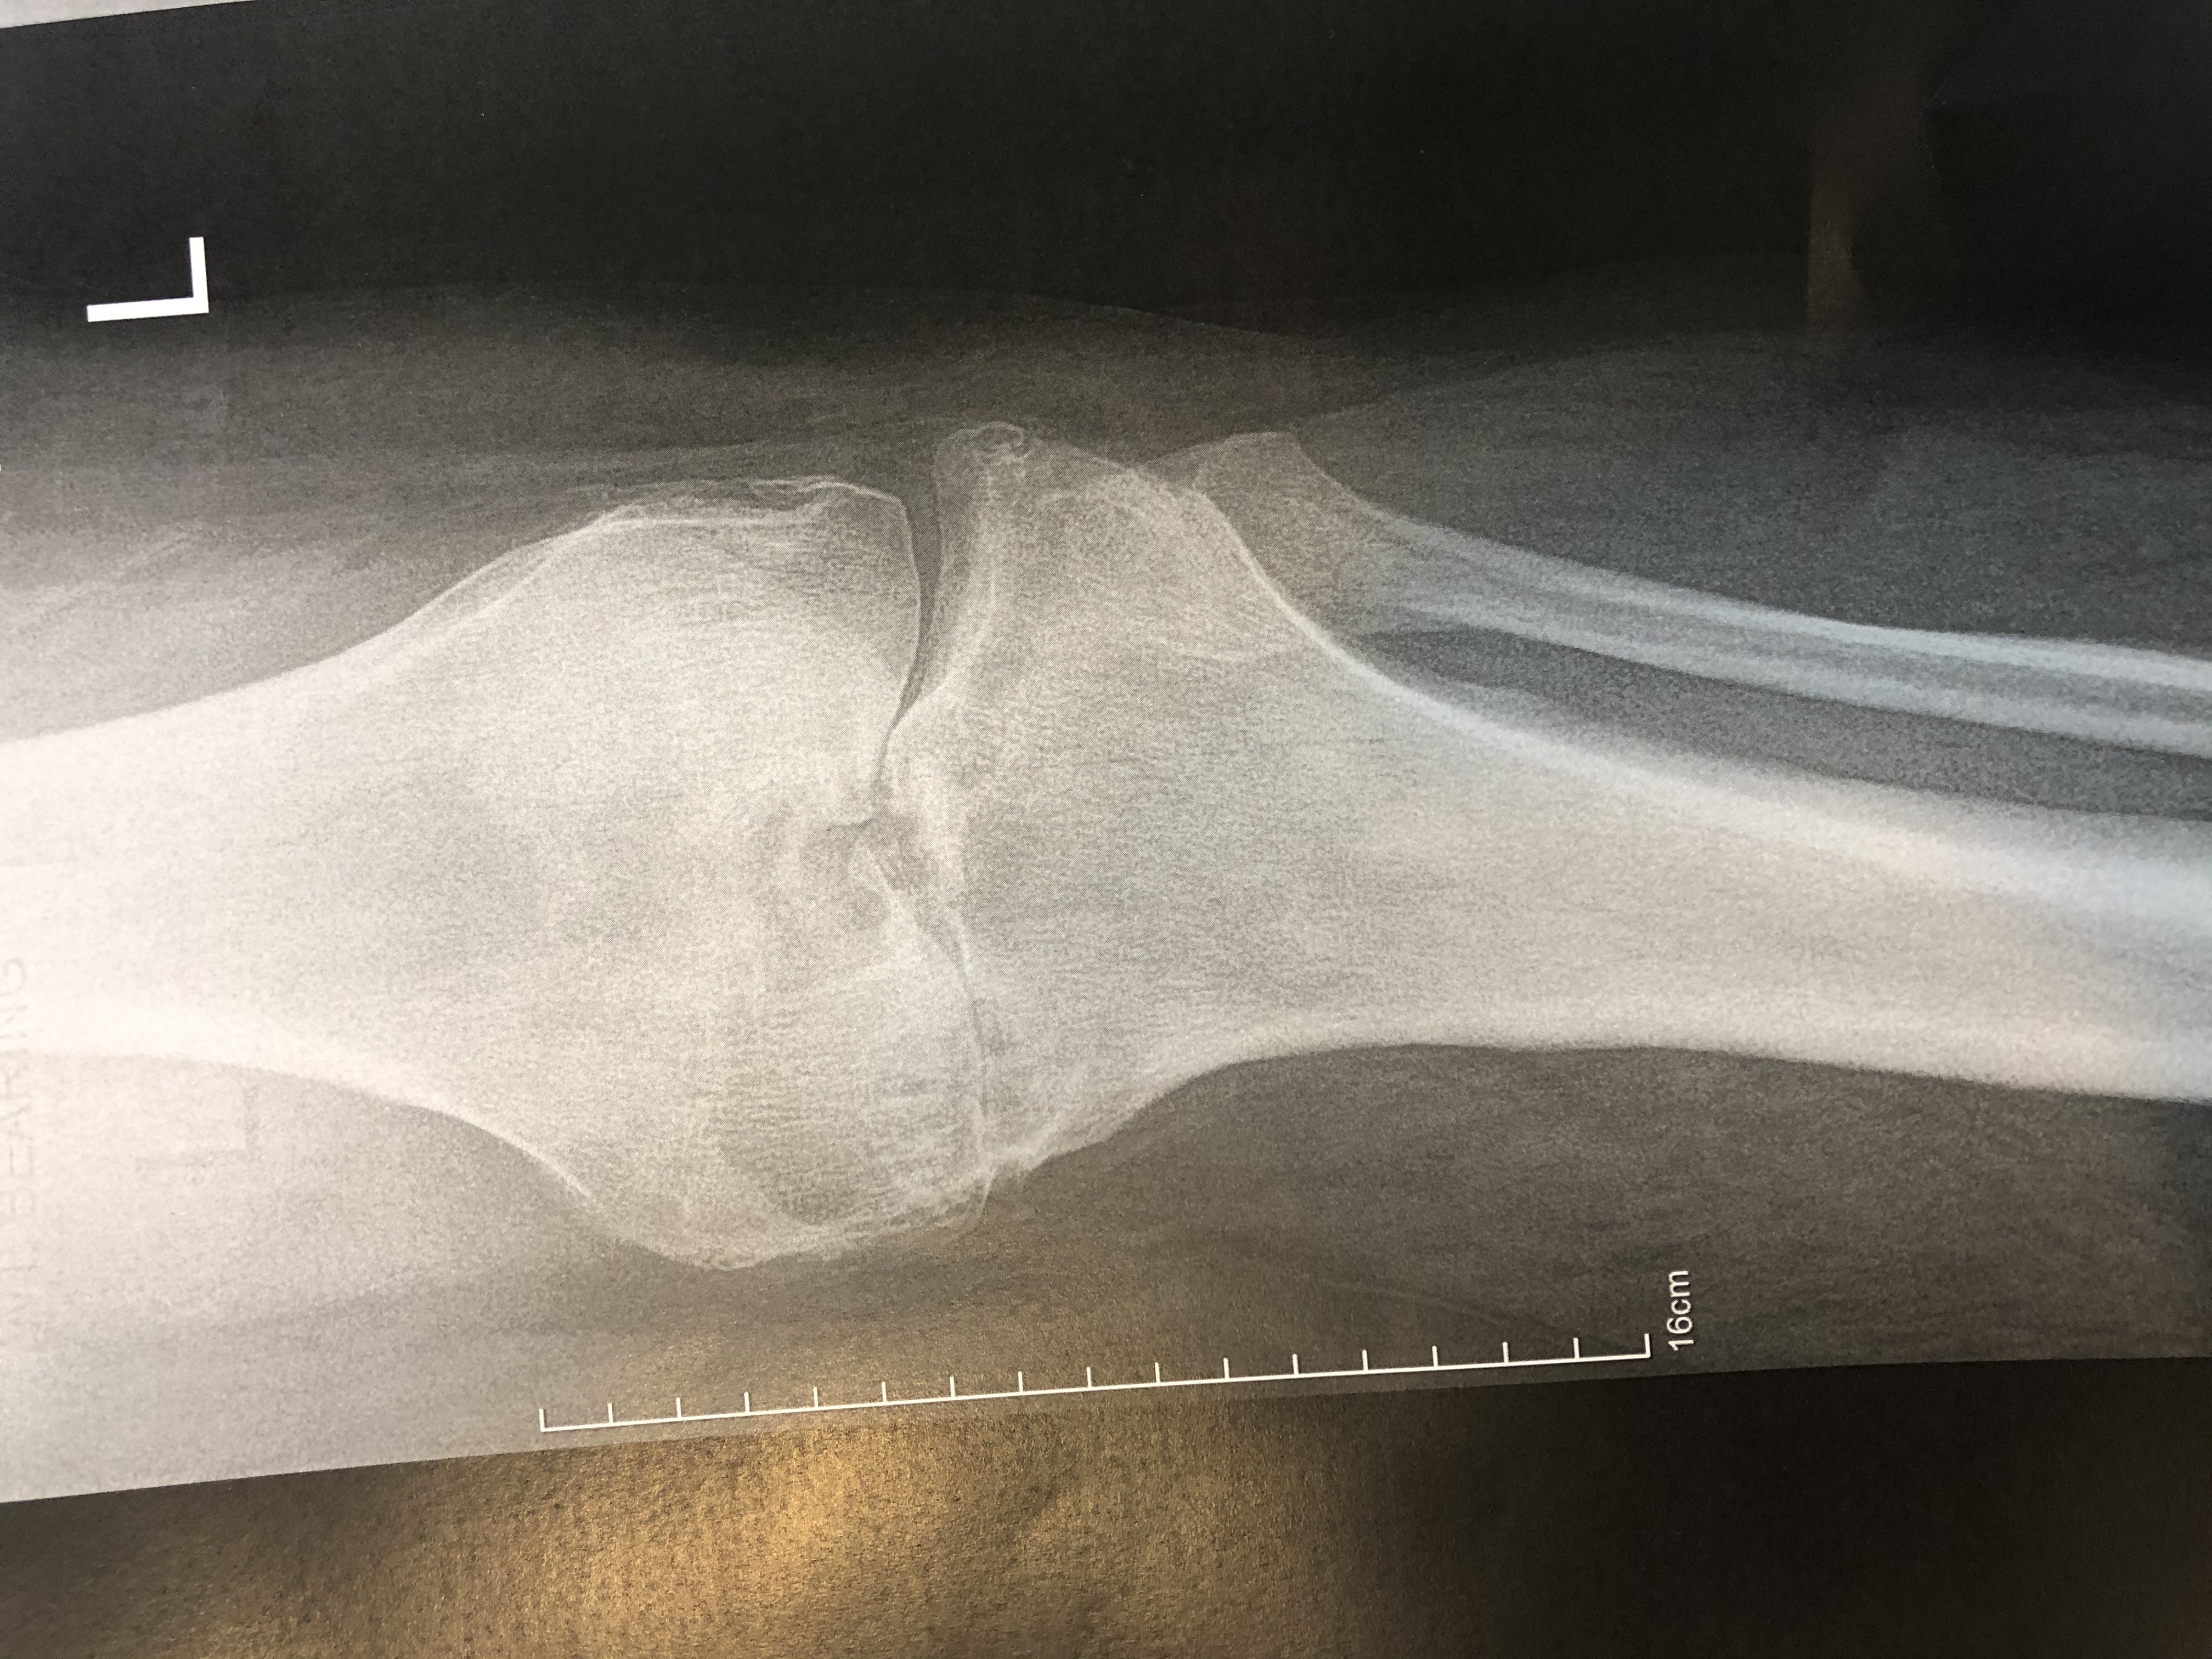

Knee Osteoarthritis

Varus OA Knee Knee Medial OA

Osteoarthritis

Osteoarthritis of the knee, also known as knee OA, is a degenerative joint disease that primarily affects the articular cartilage and surrounding structures in the knee joint. It is the most common form of arthritis and a leading cause of chronic pain and disability among older adults. Knee OA typically develops slowly over time due to the wear and tear on the joint, but it can also occur as a result of previous knee injuries or conditions that affect joint alignment.

In knee OA, the protective cartilage that covers the ends of the bones within the knee joint gradually deteriorates, leading to friction, inflammation, and damage to the underlying bone. This results in pain, stiffness, swelling, and reduced range of motion in the affected knee. As the disease progresses, bone spurs (osteophytes) may develop, further contributing to joint pain and dysfunction.

The diagnosis of knee OA is typically based on a combination of clinical evaluation, medical history, physical examination findings, and imaging studies such as X-rays or MRI scans.